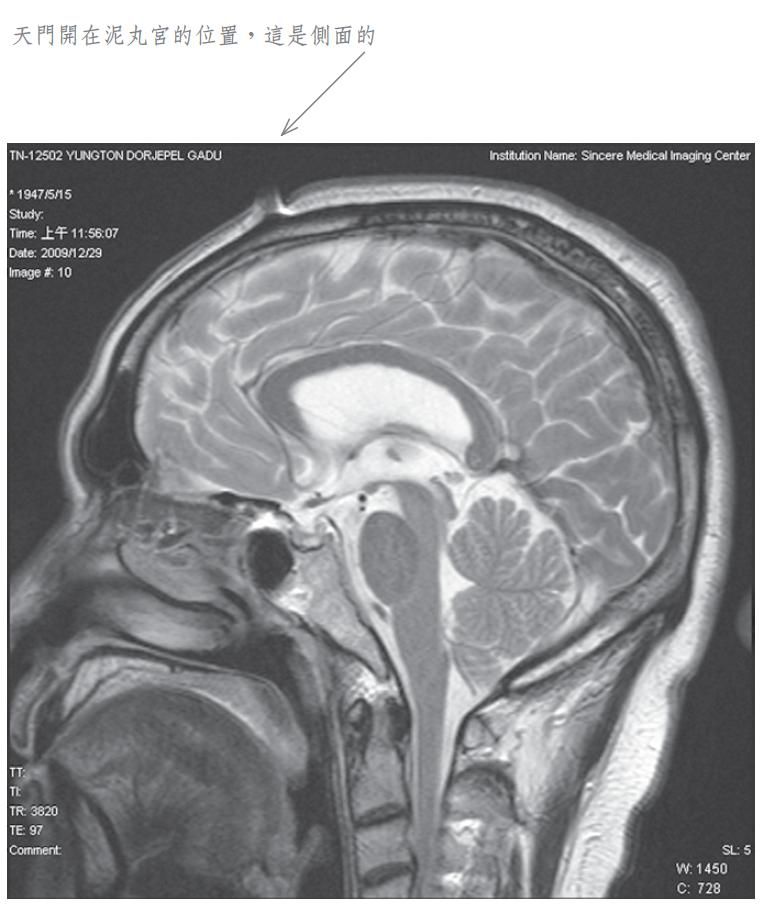

当我将此种修法中发生之觉受禀报佛陀师父时, 佛陀师父又为我传了秘密口诀。经过一段时日, 佛陀师父在公开开示的法音带中,才提到我曾经修法达到化身境的初级,即是素化身的意思。为了让众生明了佛法的伟大,事隔多年之后,我特别于二零零九年十二月廿九日,到中心综合医院安排磁振造影(MRI)头部的摄影检查,结果发现泥丸宫的部位出现一个1.5公分宽深的开口,同时拍下了有一股神识出气冲出头部的实况。负责检查的医生非常惊讶称奇,但无法解释其原因,因而将它归因于非人之所为。我其实非常清楚,我的神识化身本来就是从这里出入的,以下是在医院MRI检查的扫瞄片。